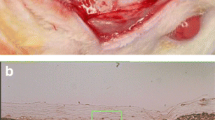

Measurements of CM thickness and collagen content in streptavidin-stained sections (reported previously ([42]) were made by superimposing three rectangular regions of interest (ROIs) per disc, one anterior, one middle, and one posterior. Each ROI had dimensions of 0.625 mm × 0.4 mm (= 0.25 mm2). A grid containing 40 μm × 40 μm cells was superimposed on the ROIs (Fig. 1) and the number of cell intersections in the grids that hit collagen within the ROI was registered. Mean residual collagen content (% of baseline) and CM thickness (mm) were determined for each disc. H&E stained sections were used to better identify the surrounding tissues (Fig. 2). For macrophage and endothelial cell counts, identical ROIs were used and all positive cells were counted within each ROI and the mean per disc was calculated.

Photomicrograph showing the 40-μm-cell grid superimposed on the ROI (stained green) overlying the disc, which is stained in red/brown with an Avidin‐biotin‐HRP reaction. The horizontal borders of the ROI are set to include the total width of the membrane disc. Methods used to measure collagen content and immunostained cells are listed in the “Methods” section